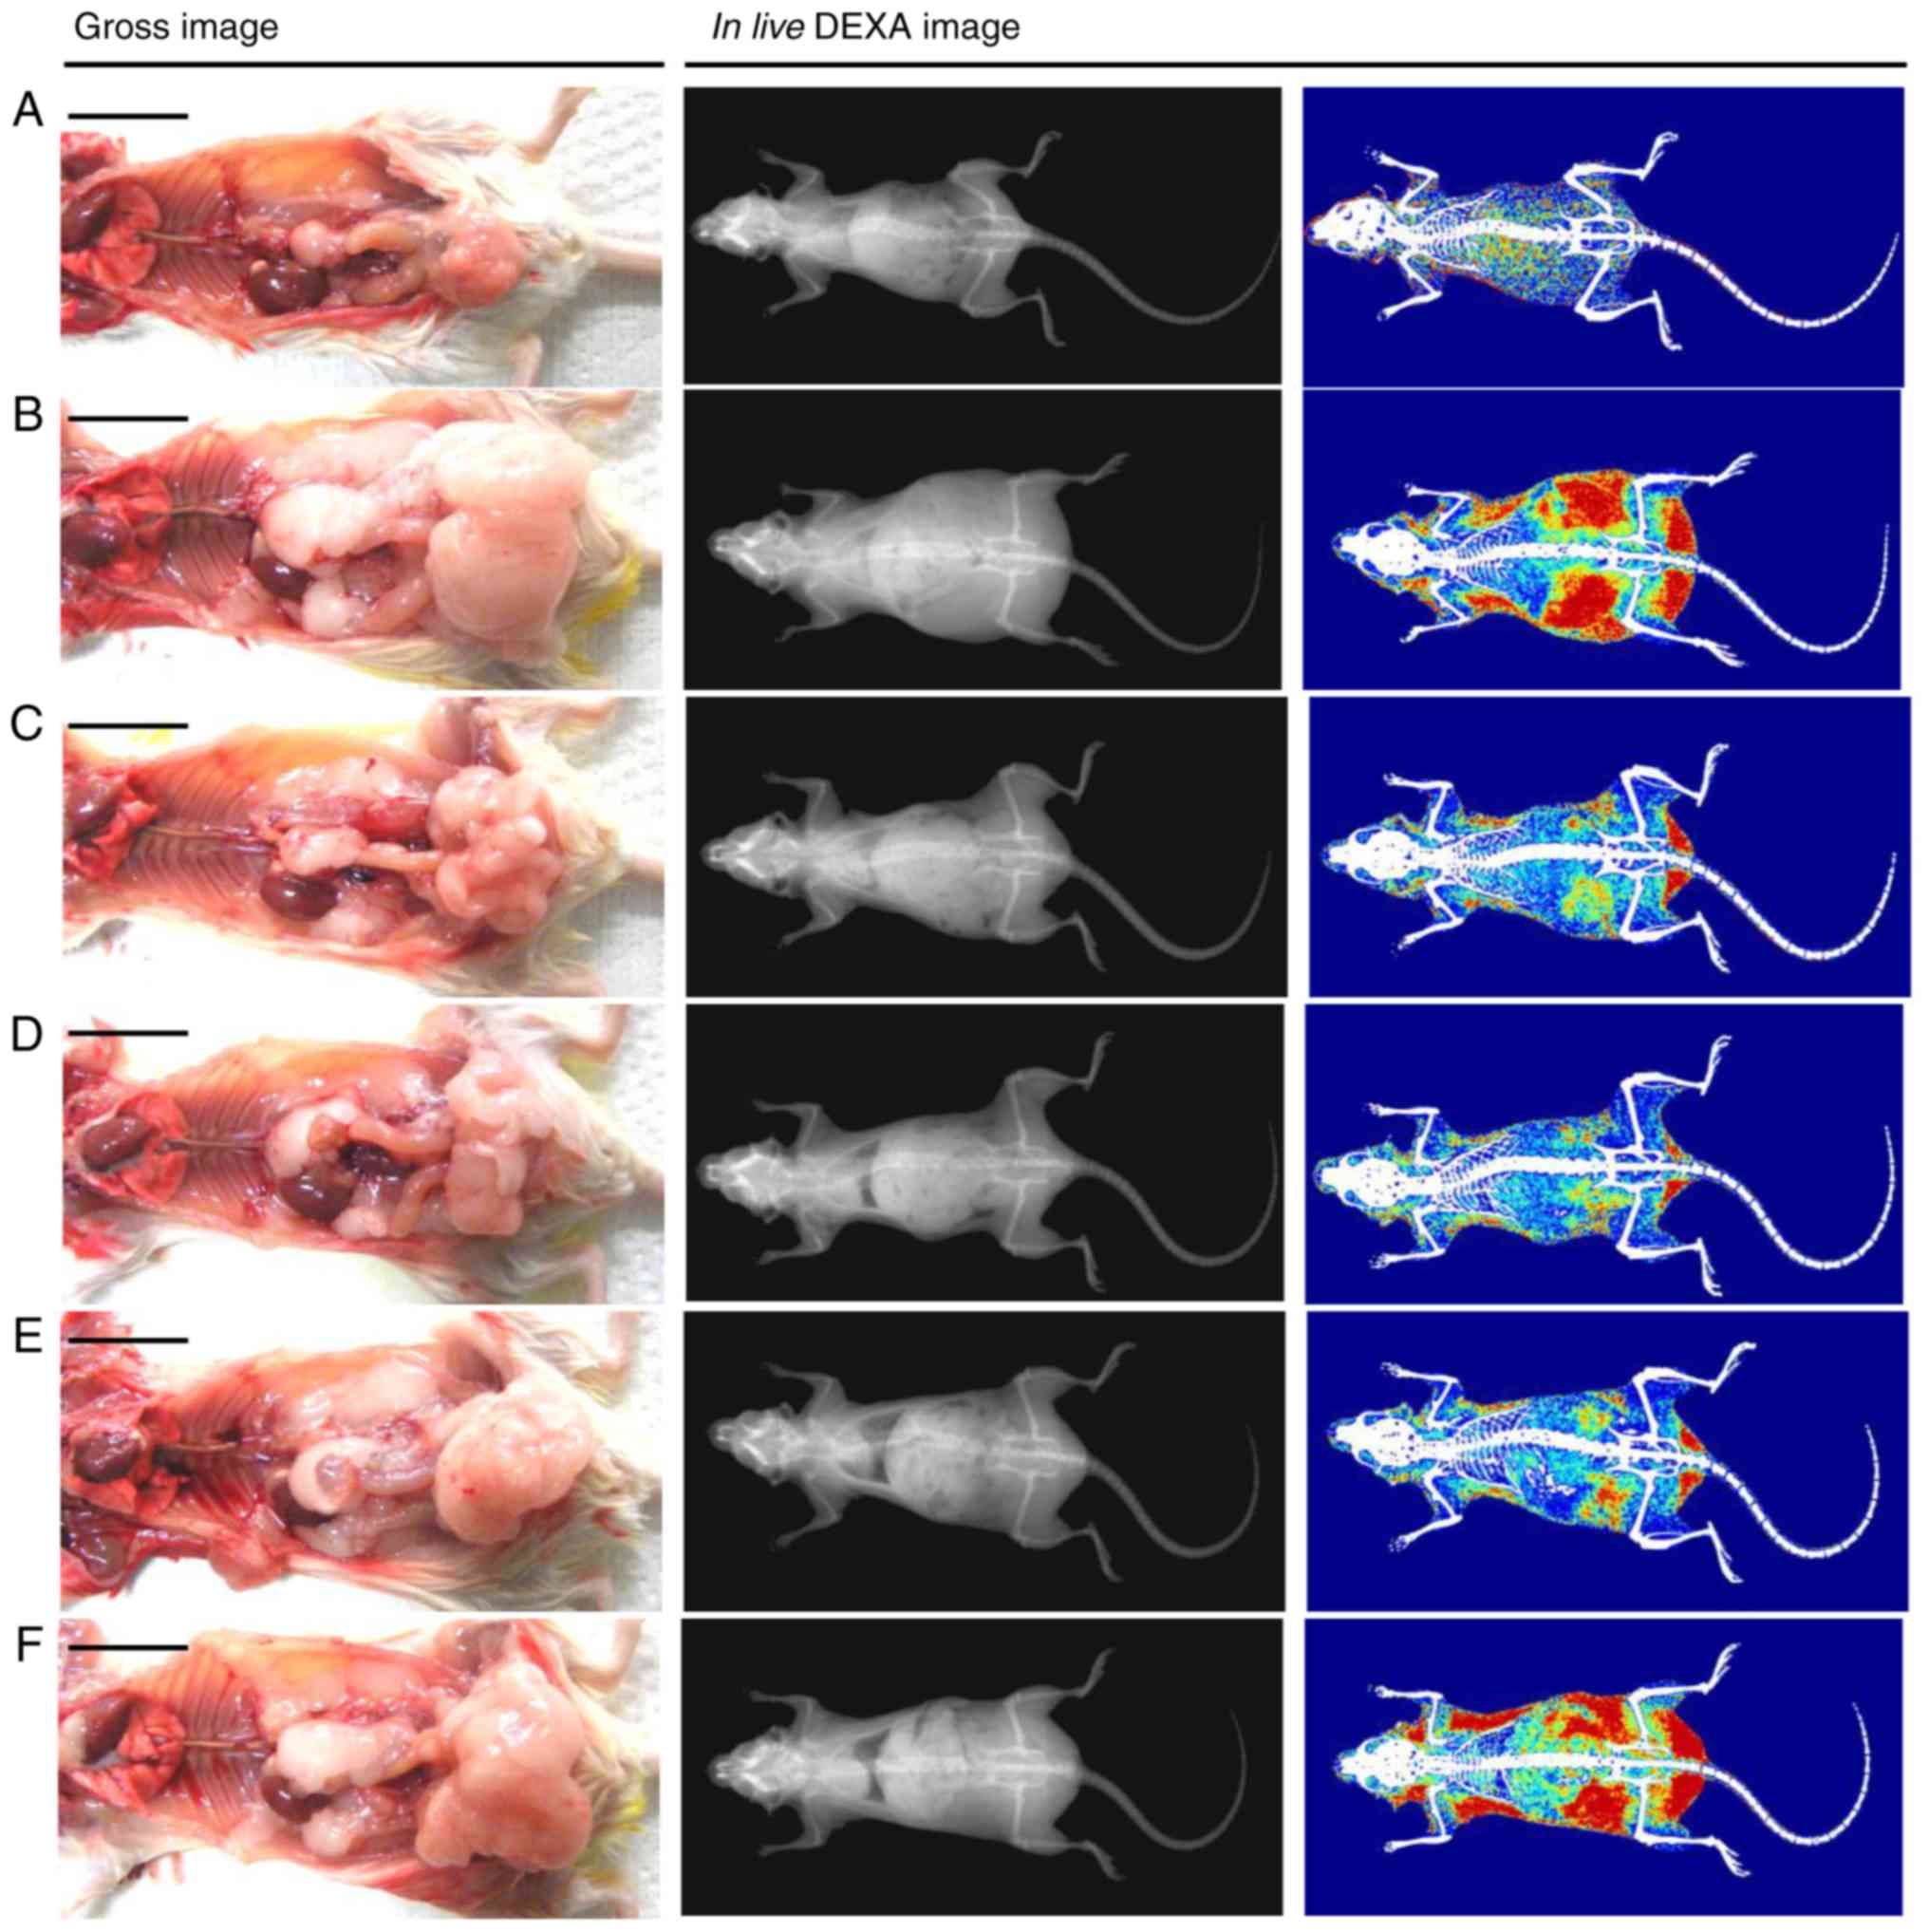

Significant (P<0.05) increases in the total body

fat and abdominal fat density was observed in the HFD control mice

compared with in the intact control, whereas a significant

(P<0.05) decrease in the total body and abdominal fat density

was observed in all treatment groups following analysis via live

DEXA. Specifically, all doses of BHe resulted in clear

dose-dependent decreases in the total body and abdominal fat

density compared with in the HFD control mice (Figs. 3 and 4). The mean total body fat density was

increased by 295.14% in the HFD control group, with changes of

−58.03, −26.29, −43.12 and −56.10% in the metformin (250 mg/kg) and

BHe (400, 200 and 100 mg/kg)-treated groups, respectively. A-55.96%

decrease in the mean abdominal fat density was observed in the HFD

control group, with changes of −55.96, −24.78, −38.78 and −54.12%

in the metformin (250 mg/kg) and BHe (400, 200 and 100

mg/kg)-treated groups, respectively.